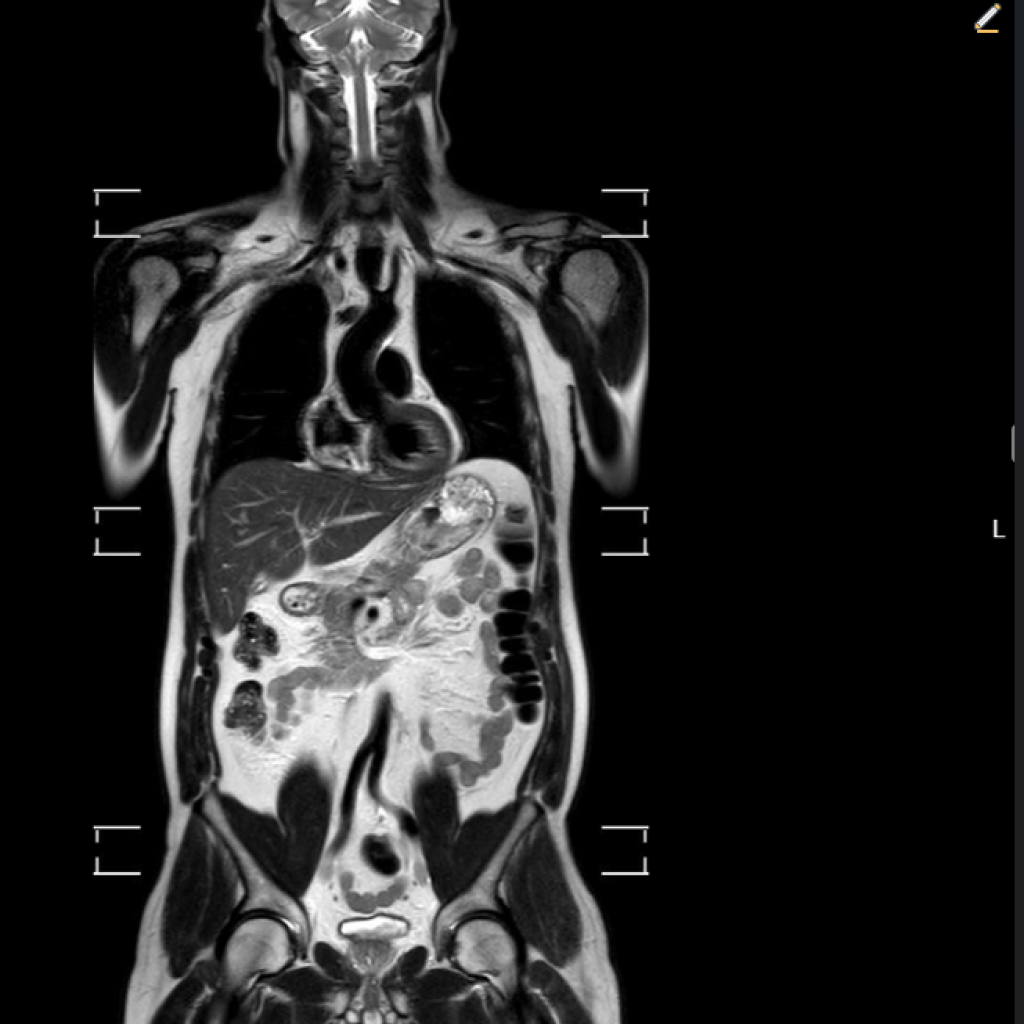

Specijalna bolnica Medico predstavila novu uslugu – magnetsku rezonancu cijelog tijela: bezbolnu, neinvazivnu pretragu za preventivnu procjenu zdravlja cijelog organizma

RIJEKA Magnetska rezonanca cijelog tijela, poznata kao MR cijelog tijela, sve češće se koristi u modernoj medicini zbog svoje neinvazivnosti i preciznosti. Radi se o bezbolnoj radiološkoj pretrazi koja omogućuje uvid u strukture čitavog organizma tijekom jednog snimanja, bez izlaganja pacijenta ionizirajućem zračenju. Ova metoda smatra se vrlo sigurnom te je najčešće namijenjena osobama s povećanim rizikom za razvoj zloćudnih bolesti, ali i onima koji žele preventivno provjeriti svoje zdravstveno stanje. Osim za ranu detekciju tumora i upalnih procesa, MR cijelog tijela često služi kao dopuna drugim radiološkim pregledima.Snimanje se izvodi u trajanju od oko 40 minuta, dok cijeli proces prosječno traje sat vremena. Pregled se obavlja bez korištenja kontrastnog sredstva i bez zračenja, a za pacijente s izraženom nelagodom u skučenom prostoru moguće je snimanje uz kratkotrajnu sedaciju.

U sklopu jednog snimanja, MR omogućuje prikaz mozga, struktura prsnoga koša, trbušnih organa poput jetre, žučnog mjehura, gušterače, slezene i bubrega, zatim nadbubrežnih žlijezda, zdjeličnih organa (mokraćni mjehur, rektum, maternica i jajnici kod žena te prostata kod muškaraca), kao i cijelu kralježnicu – vratnu, prsnu i lumbalnu. Pregled pruža orijentacijski uvid u stanje organizma i može otkriti eventualne promjene koje zahtijevaju dodatnu obradu. Nakon pregleda pacijent dobiva preporuke za daljnju dijagnostiku i eventualne terapijske postupke, čime se olakšava pravovremeno donošenje odluka o zdravstvenoj skrbi.